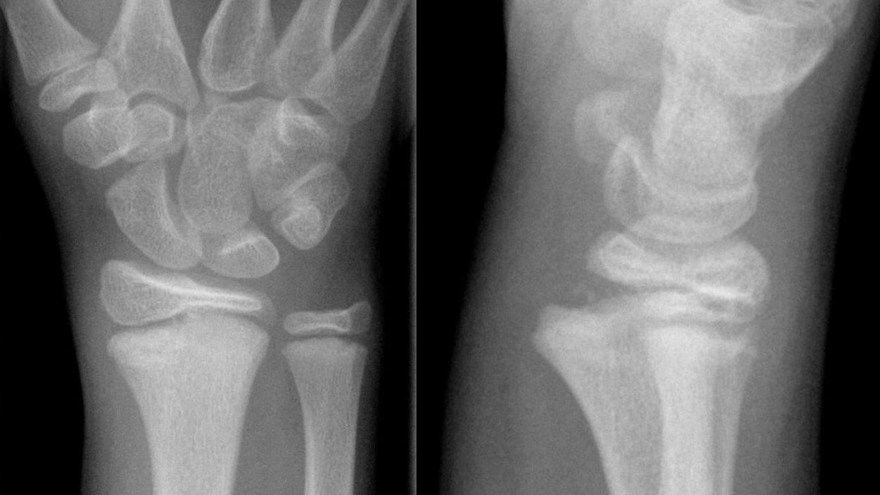

Scaphoideumfraktur

Symtom

Palpationsömhet i fossa Tabatiére, smärta vid axialt kompression av tummen samt vid dorsalextension respektive radialdeviation av handleden.

Drabbar ofta yngre individer i samband med sportutövning eller efter annat kraftigt dorsalextensionsvåld. Frakturen är ofta svår att identifiera på slätröntgen varför upprepade undersökningar och/eller CT/MR kan behövas.

Scaphoideum är dåligt vaskulariserad och ofta läker dessa frakturer (ffa proximala polfrakturer) långsamt; 3 månader i gips är normaltid! Gipsen skall immobilisera tumbas, handled och begränsa armens pro-supination. Utebliven läkning (pseudartros) är relativt vanligt och risken ökar om frakturen inte immobiliseras från skadetillfället.

Vid misstanke om scaphoideumfraktur (adekvat trauma, ömhet i fossa Tabatiére)

- Immobilisera i scaphoideumgips även om röntgen bedöms normal.

- Beställ då röntgenkontroll (utan gips) efter 10-14 dagar! Om röntgen är u a även efter 2 veckor, men status kvarstår: ordna snar MR- eller CT-undersökning!

Om skadan missas leder den mycket ofta till pseudartros och senare artros. En smärtsam pseudoartros kräver ofta att man tillför ben från crista illiaca vid operation och vid en handledsartros krävs någon typ av steloperation eller annat större ingrepp.

Det är tyvärr vanligt att frakturen missas då patienten kan uppleva symtomen som en distorsion, men det är också ganska vanligt att det missas av den undersökande doktorn. Detta sammantaget (s.k. 'patient's and doctors’ delay') innebär tyvärr att pseudoartrosoperationer är ganska vanliga.